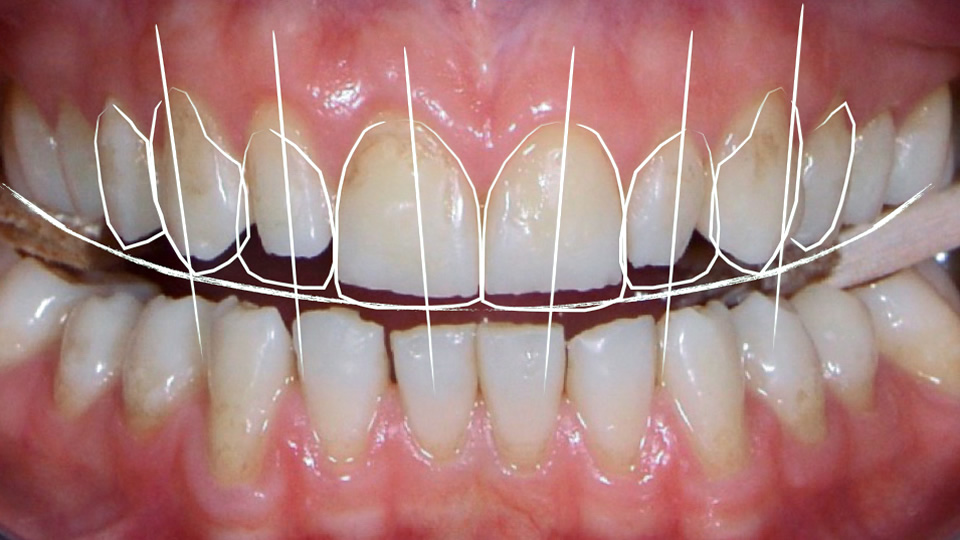

Digital Smile Design (DSD) is an innovative concept developed by the Brazilian star dentist Dr. Christian Coachman. The special analysis and planning method allow to simulate and visualise the patient's desired smile even before treatment. The key is to create harmony between teeth, lips, and face.

Aesthetic facial lines are drawn and the smile is analysed. The patient can determine the desired tooth length and shape and create a perfect smile.3. Teamwork dental technique